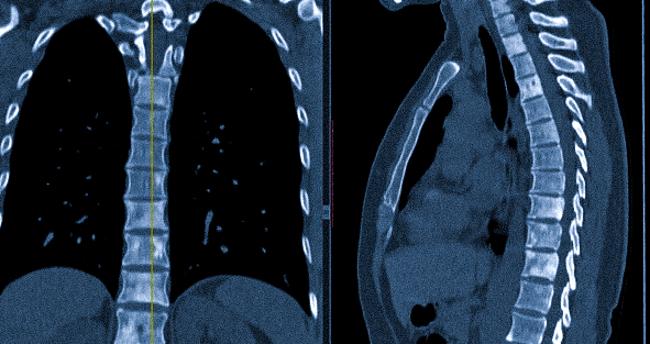

В ходе выполнения компьютерной томографии используется рентгеновское излучение. Коллиминированные лучи обеспечивают возможность настраивания ширины шага, что помогает устанавливать толщину сканируемого среза. Ионизирующие потоки частично поглощаются тканями организма, а степень рентгеноконтрастности меняется от плотности материала. На томограммах кости и хрящи отображаются в светлых тонах (гиперденсный сигнал), в то время как более мягкие анатомические структуры выглядят как темные области.

Процесс сканирования осуществляется в аксиальной плоскости. На основе поперечных срезов происходят реконструкции фронтальных и боковых проекций, а также создаются 3D-модели позвоночника. Это трехмерное изображение позволяет детально понять расположение метастазов, степень повреждения паравертебральной области, спинного мозга, нервных корешков и сосудов.

КТ показывает очаги деструкции костных, хрящевых элементов, переломы, трещины в области тел и отростков. При нарушении формы позвоночного канала возможно сдавление спинного мозга, повреждение нервной ткани.

Компьютерная томография позволяет выявлять патологические изменения, а также определять характер поражения и вовлечение соседних тканей.

Остеоидная остеома на снимках может демонстрировать различную степень окостенения и может сопровождаться отечностью костного мозга рядом с ней, хотя иногда не визуализируется из-за изменений в окружающих тканях. Вокруг неё присутствует участок со признаками плотного склероза и вариациями степени выраженности периостальной реакции. Возможно утолщение листков плевры или наличие плеврального выпота. Основной особенностью опухоли является наличие локальной сколиотической деформации с формированием вогнутой дуги со стороны остеоидной остеомы.

Характерные для остеоид-остеомы изменения на КТ и МРТ могут имитировать картину злокачественной опухоли, что иногда провоцирует ложное диагностирование онкологии.

Остеобластома позвоночника на изображениях выглядит как четко очерченное экспансивное образование с краями, напоминающими контуры географических объектов. Чаще всего она обнаруживается в дуге позвонка и распространяется на его тело. При этом наблюдается узкая переходная зона с склерозированной границей. Дополнительно могут быть зафиксированы воспалительные изменения в области соседних рёбер, утолщение плевры и плевральный выпот, а также отечность тканей вокруг опухоли, связанная с продукцией простагландинов клетками опухоли.